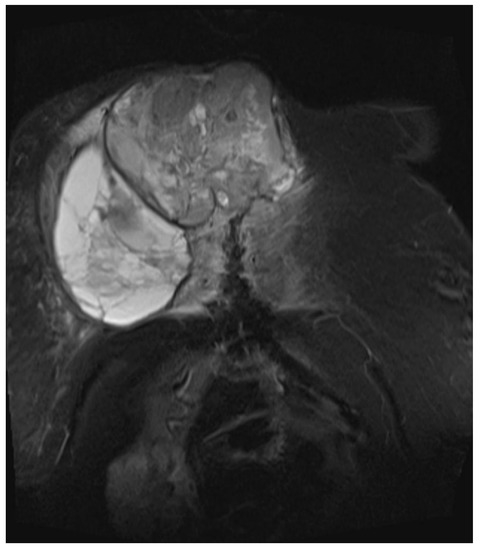

Figure 4.

Magnetic resonance imaging (MRI 2018) showing the large tumorous masses on the anterior thoracic wall, infiltration of the mediastinum per continuitatem, and contact with the aorta.

Figure 5.

Magnetic resonance imaging (MRI 2018) showing the bis soft tissue structure, partially calcified and infiltrating the sternum.